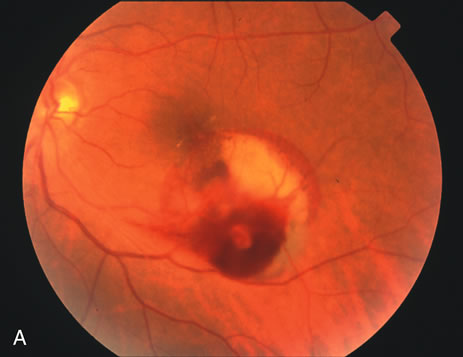

The hallmark for diagnosis of the retinal arterial macroaneurysm is visualization of the macroaneurysm itself (Fig. 1). Because of their relatively large size, macroaneurysms are not usually confused with the microaneurysms of diabetic retinopathy or branch retinal vein occlusion. Microaneurysms typically have a diameter of only 50 to 75 microns and arise from the deeper retinal capillaries; macroaneurysms on the other hand range in size from 100 to more than 500 microns in diameter and arise from the larger retinal arterioles.

Fig. 1. A. Color fundus photograph of a retinal arterial macroaneurysm 750 microns in diameter associated with circinate hard exudates and macular edema involving the fovea. B. High magnification photograph of the same macroaneurysm.